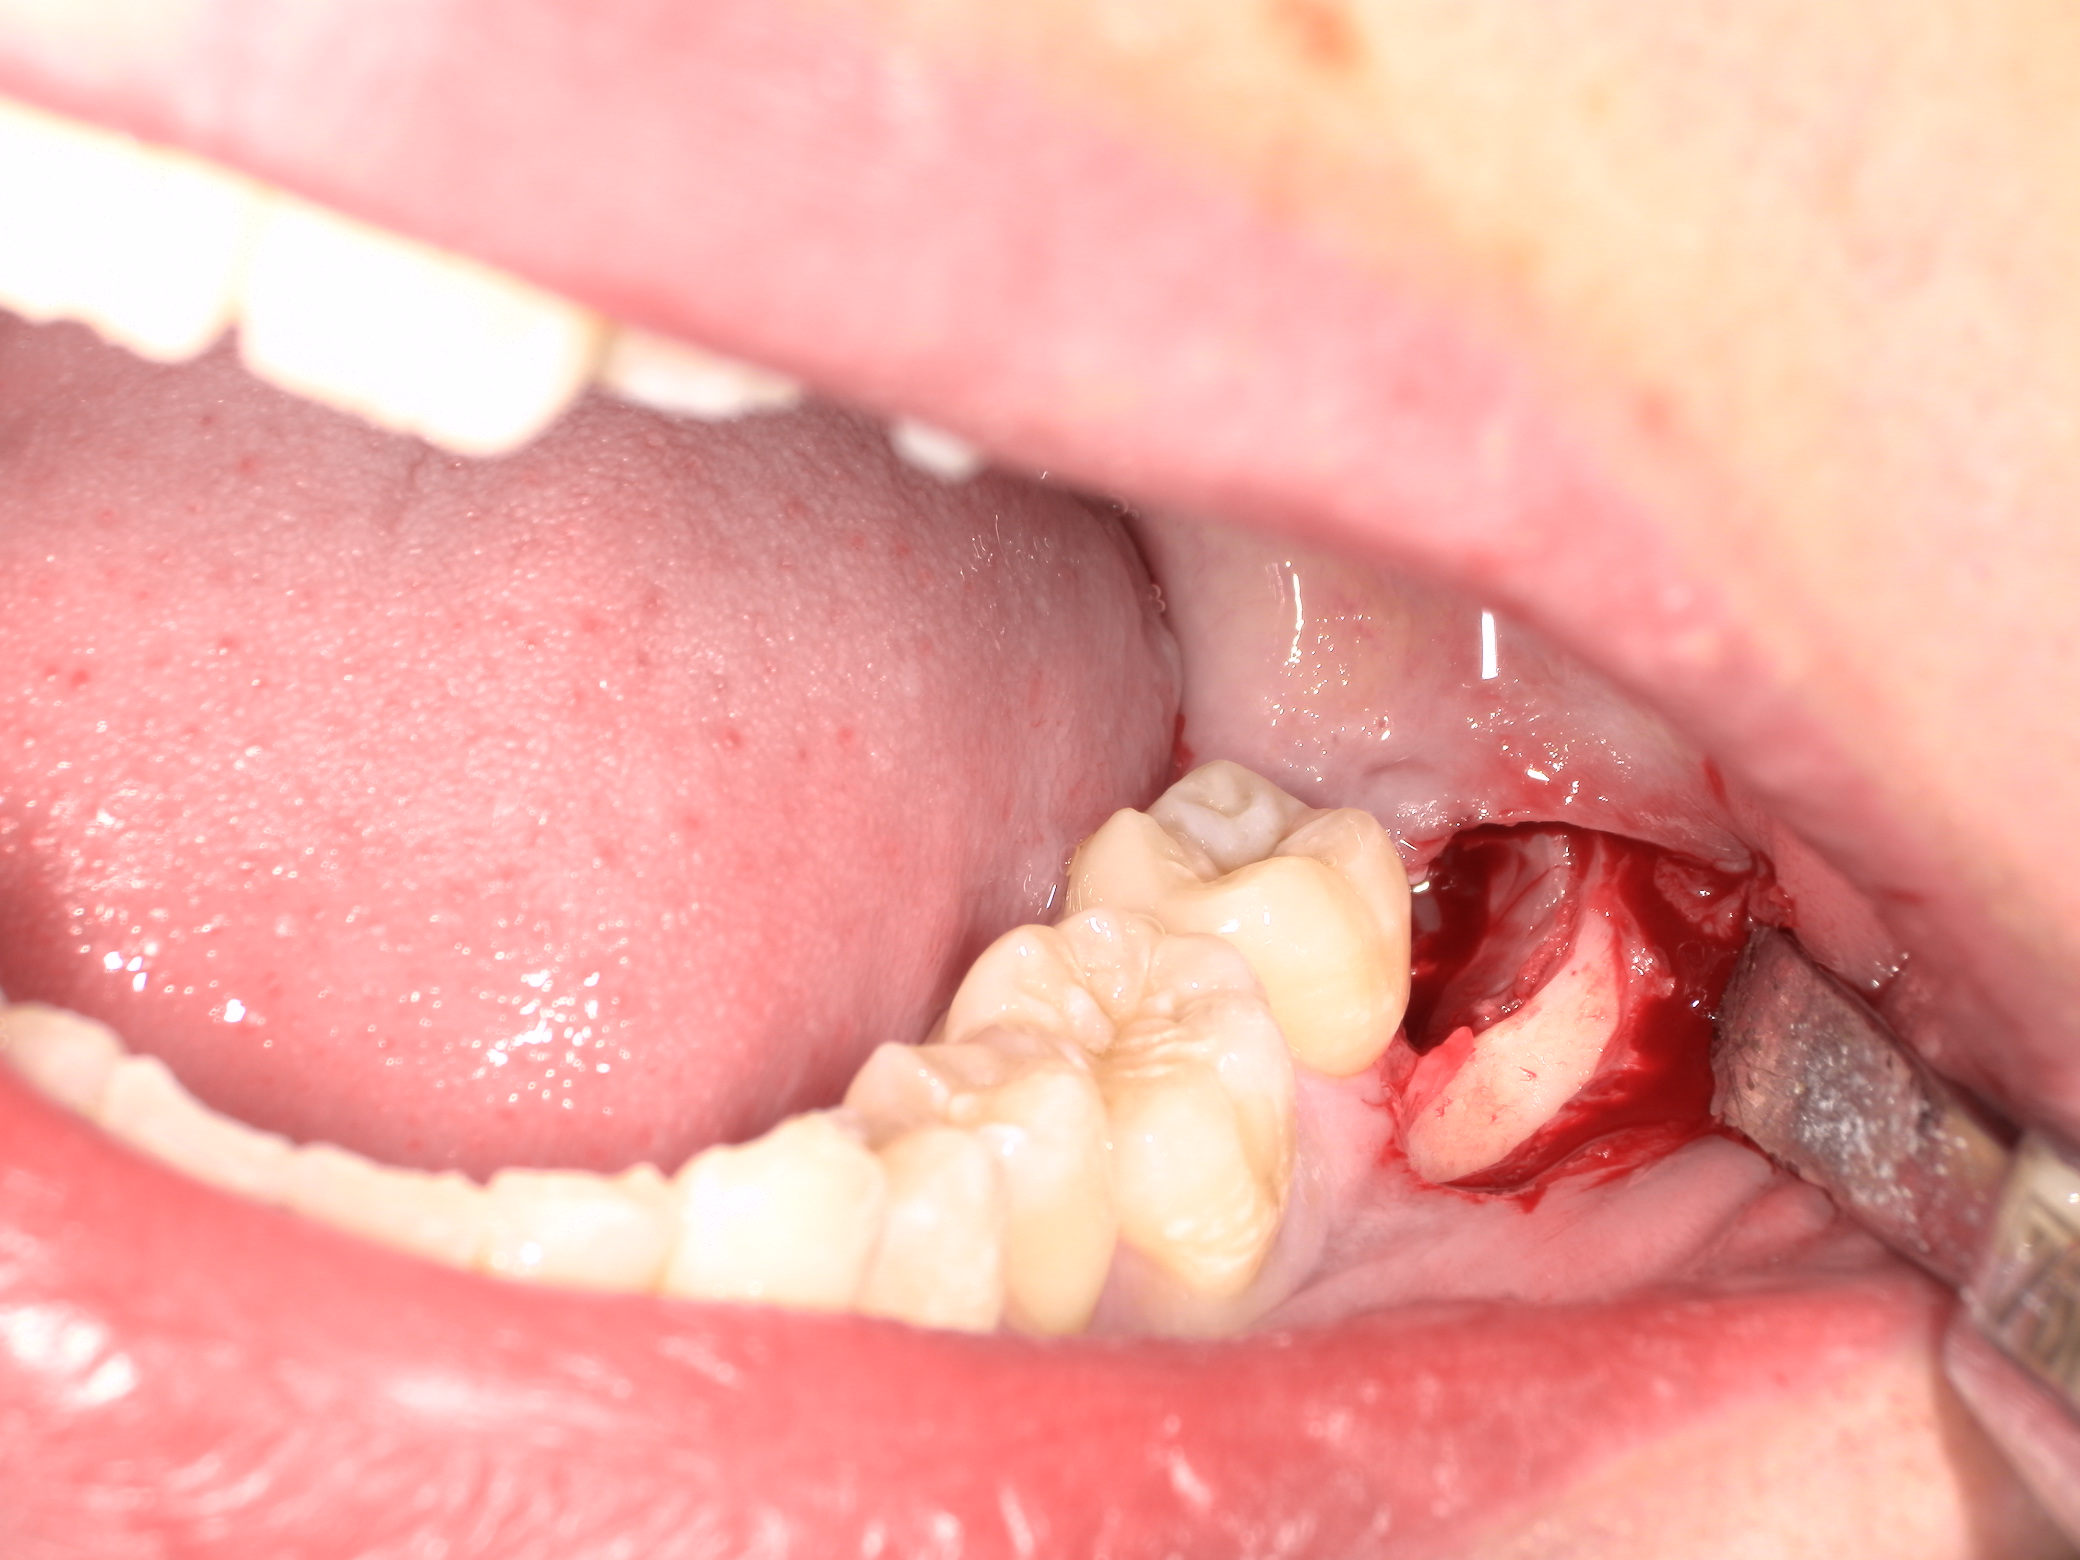

親知らずは歯茎と骨の中に埋まっています。

将来、智歯周囲炎や手前の歯に悪影響が及ばないように抜歯することとなりました。

事前にCTを撮影し位置や方向だけでなく、歯冠・歯根形態も把握済みです。

切開して歯冠部周囲の骨を削ります。

頭を囲む骨はなくなり、親知らずの歯冠部が見えてきましたがまだ抜けません。歯は基本的に頭側の方向にしか抜けません。